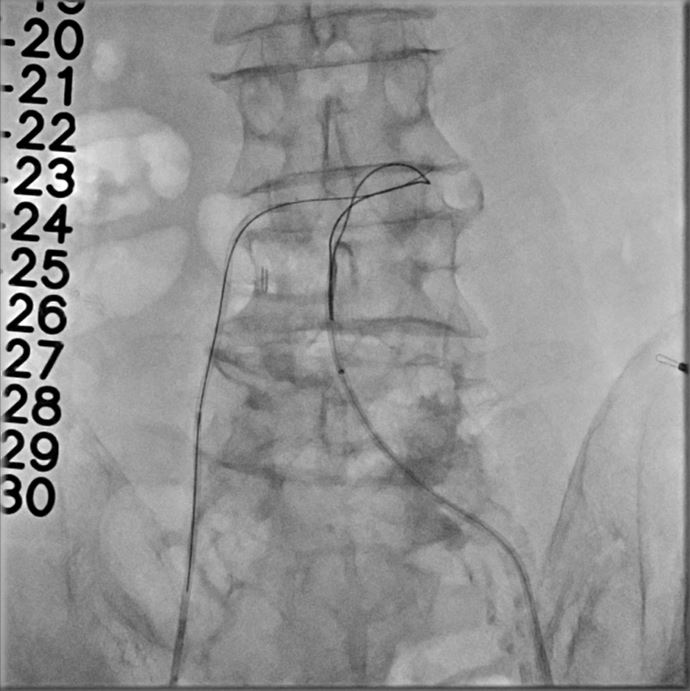

However, multislice CT scan revealed severe stenosis and calcific change in bilateral femoral arteries, making the transfemoral arterial approach unfeasible. Alternative access sites, including bilateral carotid and axillary arteries, were also not feasible. Although there was severe calcification in the abdominal aorta, the transcaval approach targeting a calcium-free segment of the aorta at the L3 level represented barely the last resort for carrying out TAVI procedures.

The transcaval approach starts with descending abdominal aortography. A 7-F renal double curve guide catheter which was advanced through the right femoral vein. An Astato wire along with a CXI microcatheter were advanced through the catheter to the indexed L3 level for transcaval puncture with the distal end of the Astato guidewire connecting with an electrosurgery pencil. After the Astato guidewire cross the vena cava and the adjacent aortic wall, the Asatato-CXI system was then captured by a 25 mm Gooseneck snare placed at the corresponding aortic level through left femoral atery, and sent upward to the thoracic aortic level. The Asatato wire was exchanged for a Lunderquist guidewire, through which an 20 French long sheath was advanced through RFV to the abdominal aorta. Standard TAVI procedures employing a Navitor 27 mm transcatheter heart valve were then performed through this vena-aortic connection facilitated by LV on-wire pacing. At the end of the procedure, an Amplatzer Duct Occluder was deployed to close the aorto-caval tract, with post-procedural angiography confirming a patent fistula with cruciform contrast flow around the neck of the occluder but with contrast returning to the cava. After careful examination, there was no extravasation on the digital subtraction angiogram. The next day, a follow-up angiogram of the aorto-caval fistula was performed, which revealed a patent fistula but without extravasation. The patient is doing well during one year of follow-up.